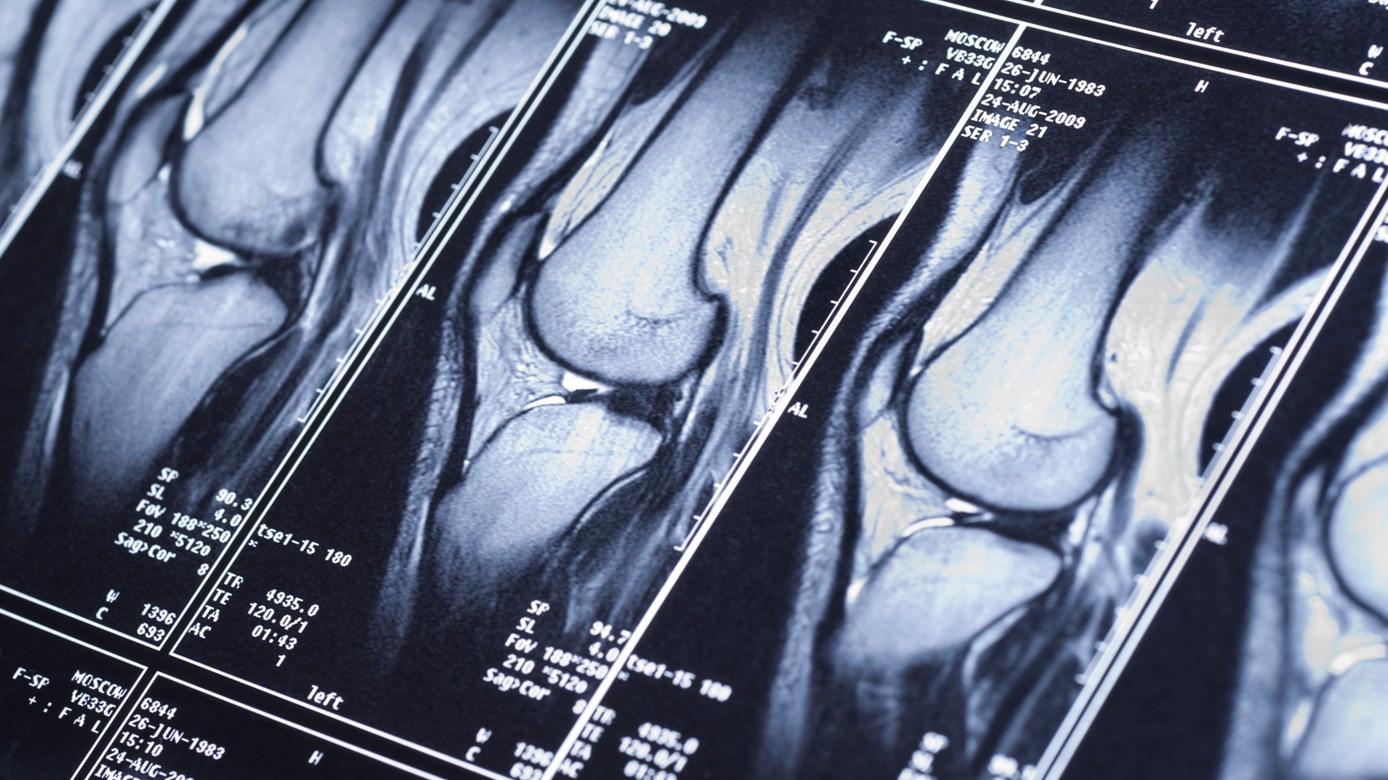

The patient has an injury to the cervical spine, lumbar spine or knee that meets the criteria outlined in the MRI Clinical Pathways.

- Knee diagnostic imaging pathway